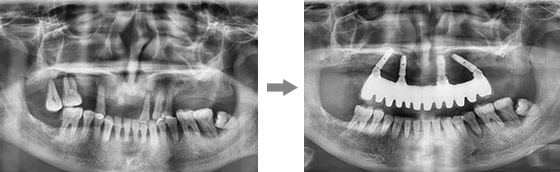

传统的种植牙种半口需要至少半年的时间,而康贝佳先进的ALL-ON-4微创即刻用种植技术,恢复半口牙仅需要植入4-6颗种植体,同时可以实现当天种牙当天用。

康贝佳胡主任为李大爷做了详细的口腔检查,并采用了ALL-ON-4技术,整个手术过程仅仅30分钟,只需4颗植体就恢复了半口牙,不仅创伤小、疼痛轻,恢复快,且为李大爷省了近一半的费用。

对于年纪较大、体弱、半全口缺牙中老年人来说,采用ALL-ON-4微创即刻用种植技术,采用斜拉式力学设计利用多个天然承重点,4颗牙根便可承受来自多方向的力即可恢复半口牙,在骨量严重萎缩的情况下,也无需植骨。并且甚至可以实现当天种植当天用,同时节省至少1/3的费用。

从术前诊断、手术种植、术后修复等一体化流程,通过口腔数字全景检查和CT片、牙槽骨条件测量、三维模拟种植、血常规检查,制定个性化专属种牙方案,根据缺牙老人的时间、费用、年纪多方面综合考虑,做到让缺牙老人放心种牙,满意种牙。